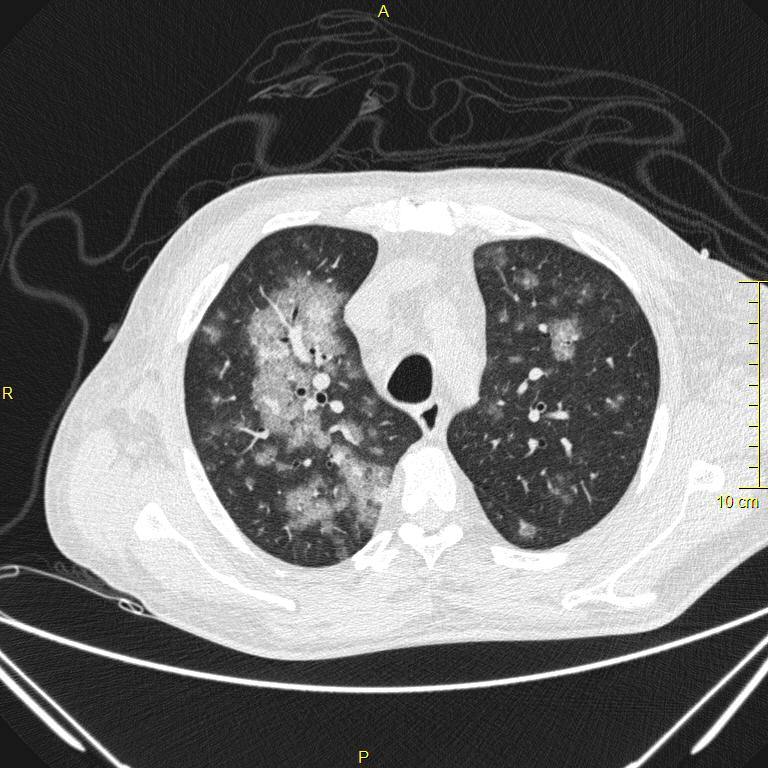

Ground Glass opacification

Histologically due to either partial filling of the alveoli (by blood, pus, water, or cells), alveolar wall thickening, or reduced aeration of alveoli (atelectasis). CT shows a hazy, gauze-like opacity, through which pulmonary vessels are still visible. As with consolidation, air bronchograms may be present.

Acute ground glass opacification has a similar differential to acute consolidation, since many fo the entities that initially cause partial airspace filling can progress to completley fill the airspaces later in the disease. The differential fo acute ground includes: pulmonary edema (which is usually dependent), pneumonia (more commonly seen in atypical pneumonia such as viral or Pneumocystis jiroveci pneumonia), pulmonary hemorrhage, ARDS.

Crazy paving

Crazy paving describes interlobular septal thickening with superimposed ground glass opacification, which is though to resemble the appearance of broken pieces of stone. Although nonspecific, this pattern was first described for alveolar proteinosis, where the ground glass opacification is caused by filling of alveoli by proteinaceous material and the interlobular septal thickening is caused by lymphatics taking up the same material.

The differential diagnosis for crazy paving includes: Alveolar proteinosis, Pneumocystis jiroveci pneumonia, organizing pneumonia, bronchoalveolar carcinoma (mucinous subtype), lipoid pneumonia (an inflammatory pneumonia caused by a reaction to aspirated lipids), acute respiratory distress syndrome, pulmonary hemorrhage